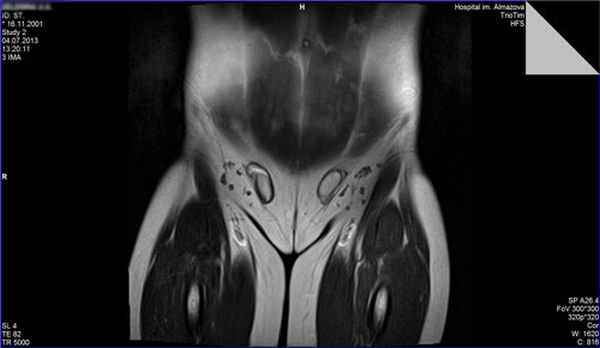

В Национальном медицинском исследовательском центре имени В. А. Алмазова функционирует Научно-исследовательская лаборатория (НИЛ) детской эндокринологии, клинической базой которой является педиатрическое отделение. Сотрудники НИЛ, являющиеся одновременно врачами-детскими эндокринологами, имеют большой опыт оказания помощи пациентам с различной патологией полового развития, включающий поликомпонентное обследование (проведение стимуляционных и супрессивных тестов для уточнения функциональной активности половых желез, визуализационные методы, иммуногистохимическое обследование, молекулярно-генетическое и цитогенетическое обследование и др.). В команде с мультидисциплинарной группой специалистов Центра (гинекологи, урологи-андрологи, клинические и молекулярные генетики, детские хирурги, психологи и психотерапевты) проводится окончательная верификация диагноза и составляется долгосрочная программа ведения пациентов. При условии регулярного мониторинга осуществляется заместительная гормональная терапия, определяется прогноз фертильности, решаются вопросы, связанные с присвоением гражданского пола, мониторинга онкологического риска дисгенетичных гонад, объема и сроков хирургического лечения. Возможно биобанкирование биологического материала с целью сохранения фертильности. Среди пациентов Центра наблюдаются дети с полной дисгенезией гонад (синдром Свайер), полной и частичной резистентностью к андрогенам, нарушениями биосинтеза тестостерона, включая редкие формы врожденной гиперплазии коры надпочечников, пациентки со сниженным овариальным резервом, синдромом поликистозных яичников и многие другие. В перспективе части пациентов с нарушением формирования пола могут быть решены вопросы фертильности путем вспомогательных репродуктивных технологий. Оказание помощи пациентам базируется на персонифицированном подходе, который возможен на основе понимания индивидуальных характеристик, в том числе с позиции молекулярной генетики, варианта патологии у конкретного больного. На снимках представлены результаты обследования некоторых из наших пациентов, продолжающих наблюдаться в нашем Центре.

НФП – полная форма резистентности к андрогенам. МРТ органов малого таза (тестикулы в паховых каналах) у фенотипически девочки с кариотипом 46ХУ.